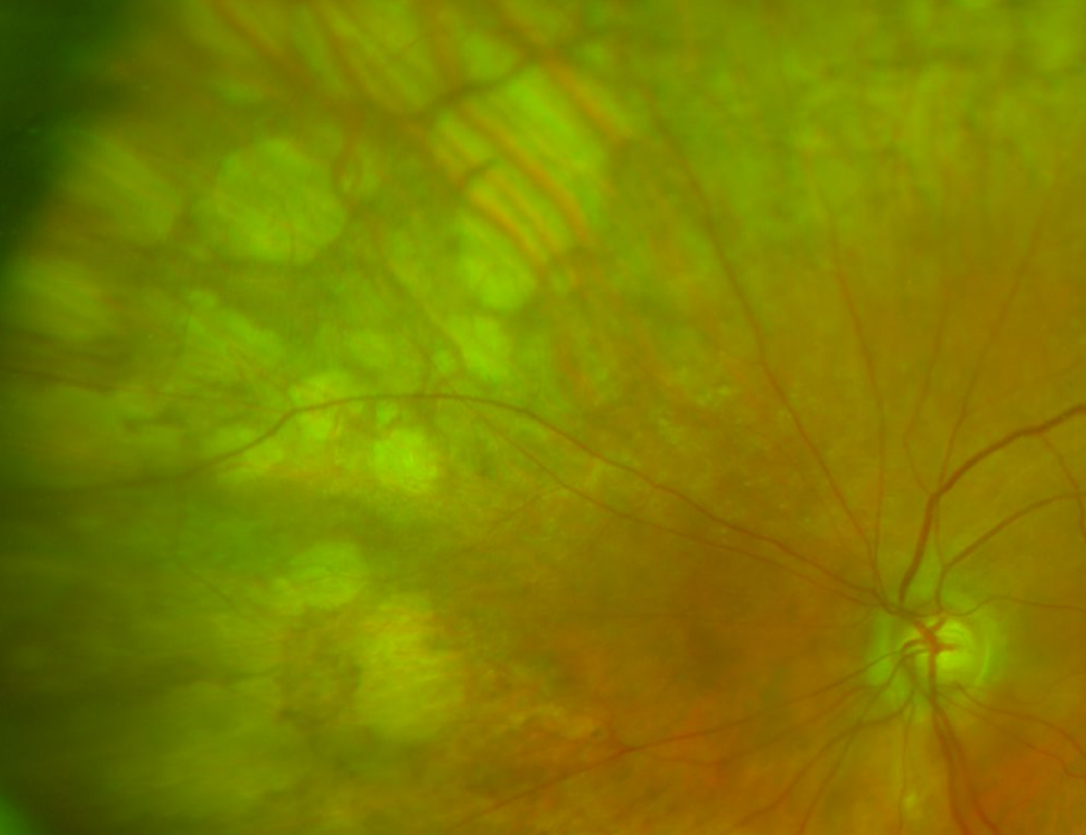

Pavingstone chorioretinal atrophy (also known as Primary chorioretinal atrophy or Cobblestone chorioretinal atrophy) is a benign retinal thinning, involving loss of the RPE and absence of photoceptors, that occurs in the peripheral retina. A strong adhesion between the retina and choroid exists in these areas. It is found more commonly in eyes with longer axial length, is often bilateral, and prevalence increases with age.

An 89-year-old female with visual acuities of 6/9+2 (20/30+2) and 6/9-2 (20/30-2) and no night vision problems or family history of inherited retinal dystrophies.

A 54-year-old Caucasian male with high myopia in the right eye (-9.50DS).

A 65-year-old Caucasian male with high myopia in the right eye (-10.50DS).